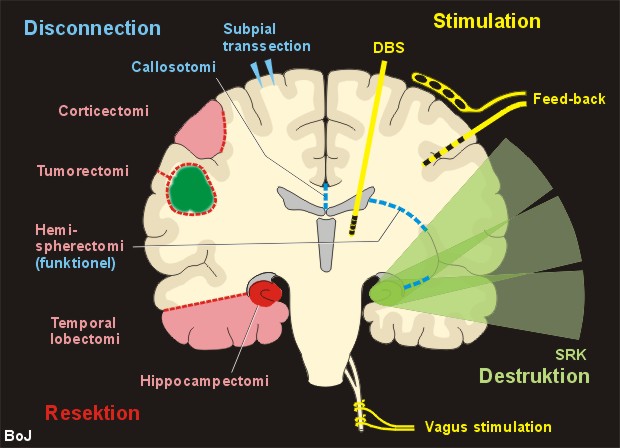

Figuren viser en oversigt over anvendte og eksperimentelle behandlinger. Fokal epilepsi kan behandles med resektion, mens mere generaliseret epilepsi kan behandles med stimulation og disconnection. Ved resektion fjernes det område hvor epilepsien starter hvorved epilepsien kan kureres ved at fjerne et relativt lille område af hjernen som måske ikke har nogen brugbar funktion pga sygdom i vævet. Der kan være tale om fjernelse af en godartet svulst som irriterer det tilstødende hjernevæv. Ved en corticotomi fjernes et tilsyneladende normalt stykke hjernebark hvor epilepsien starter. Det kan være en udviklingsdefekt i hjernevævet (cortical dysplasi) som er så beskeden at den ikke viser sig på en MR scanning. Disse "MR-negative" tilfælde stiller specielle udfordringer. Se Intrakranielt EEG.

Fjernelse af en sklerotisk (ardannet) hippocampus er den hyppigste resektive epilepsioperation. Se Hippocampectomi. Principielt kan hippocampussklerose også behandles ved destruktion af hippocampus ved fokal strålebehandling. (SRK)

Ved disconnection overskæres baner for at bremse spredningen af de epileptiske signaler. Ved callosotomi overskæres hjernebjælken delvist og ved funktionel hemisfærektomi afbrydes forbindelsen mellem den ene hjernehalvdels bark og resten af nervesystemet. Ved subpiale transektioner forsøger man at bremse dannelsen af det lokale epileptiske signal.

Ved stimulation af nervus Vagus (Vagusstimulator) eller thalamus (DBS mod epilepsi) påvirkes hjernen biokemisk så tendensen til generaliserede anfald mindskes. Der eksperimenteres med systemer som kan registrere starten af et anfald og bryde det ved lokal elektrisk stimulation i hjernen - her betegnet feed-back system.